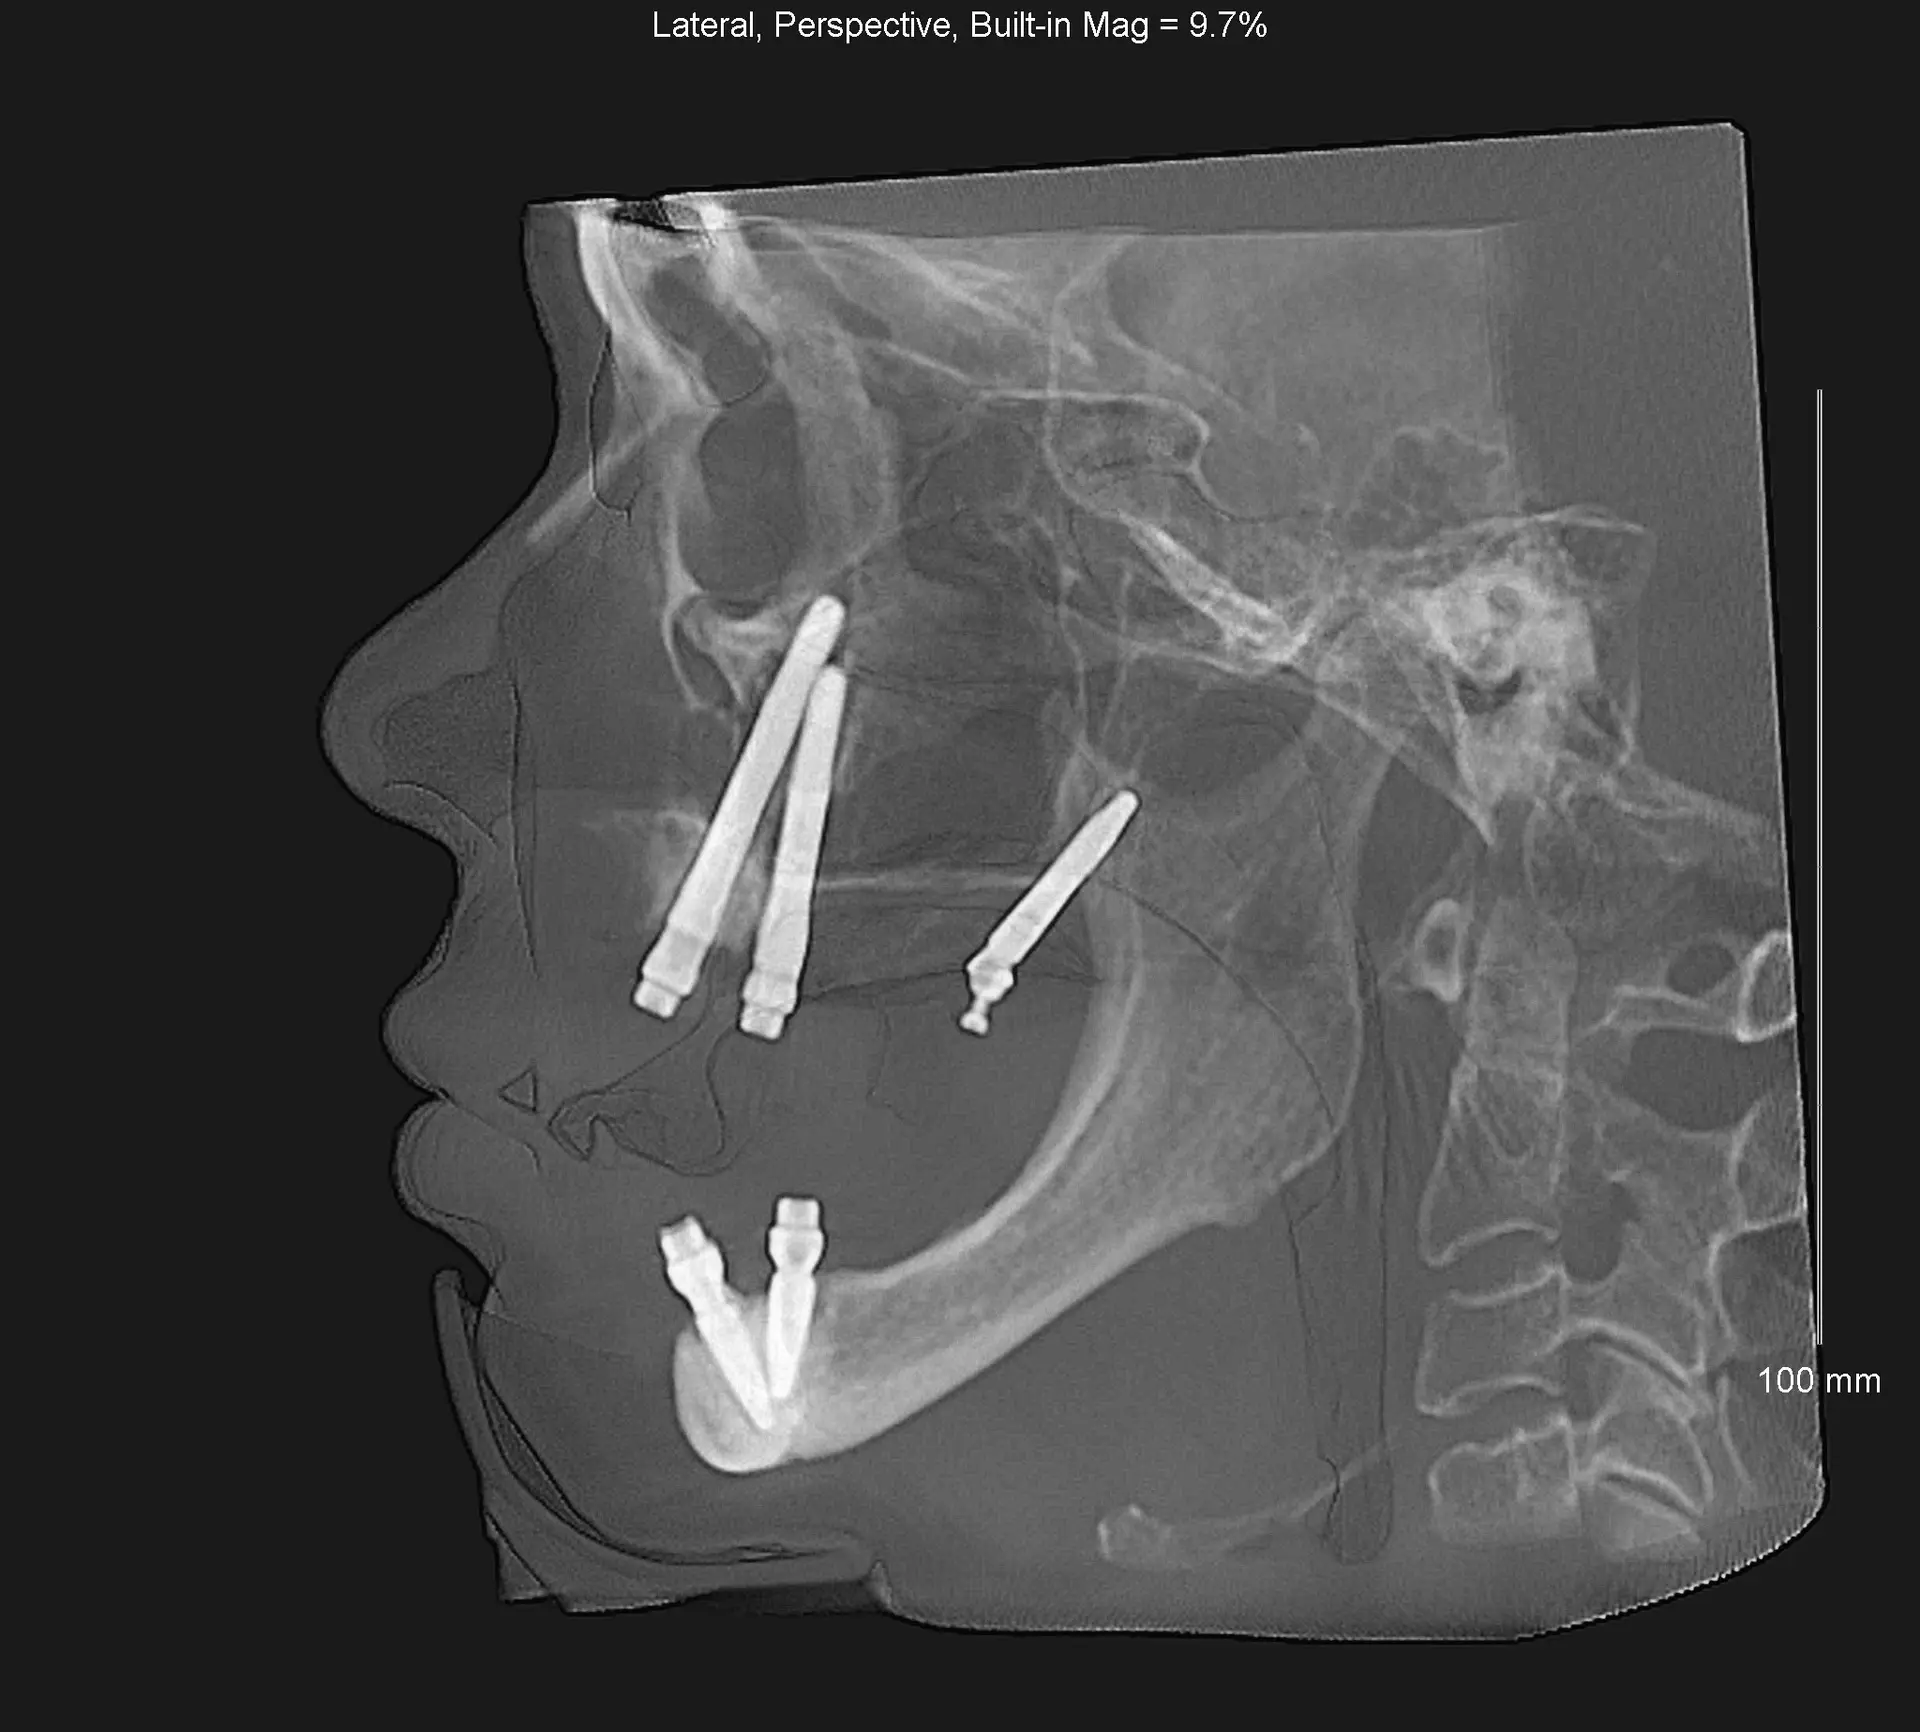

Documented case of Ana, a patient presenting with severe bone loss and failed implants. She was treated by our faculty member, Dr. Jay Neugarten, during the ZAGA Course as part of a live surgical demonstration for course participants. Treatment involved quad zygomatic implants and one pterygoid implant to improve stability. Using the ZAGA Approach, we were able to successfully rehabilitate the case despite the previous implant failures and deliver an immediate prosthesis on the same day as surgery. This case represents part of the clinical education and knowledge participants gain during the ZAGA course.